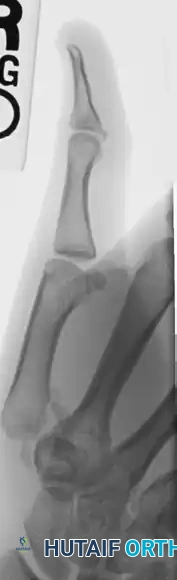

The following sequence illustrates the progression from injury to successful closed reduction and K-wire fixation into the trapezium:

Consider the case of an extra-articular thumb base fracture with 35 degrees of apex dorsal angulation in a 65-year-old male. While up to 30 degrees of angulation can sometimes be tolerated due to the compensatory mobility of the CMC joint, greater angulation requires reduction to prevent symptomatic hyperextension of the metacarpophalangeal (MCP) joint.